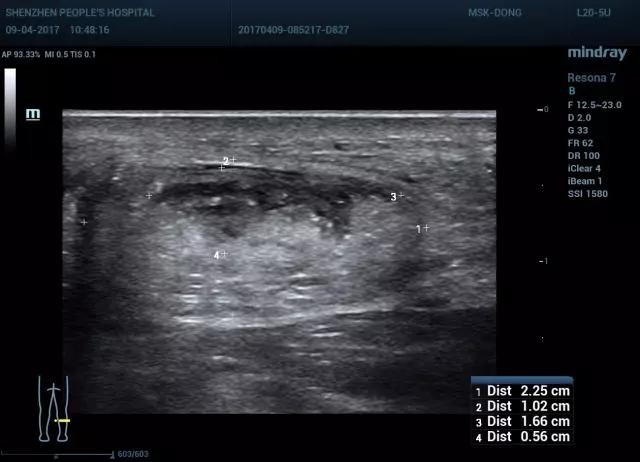

图7 跟腱部分撕裂短轴成像(显示跟腱为部分性中断)

图8 双侧对比(图右 部分撕裂,图左 正常)